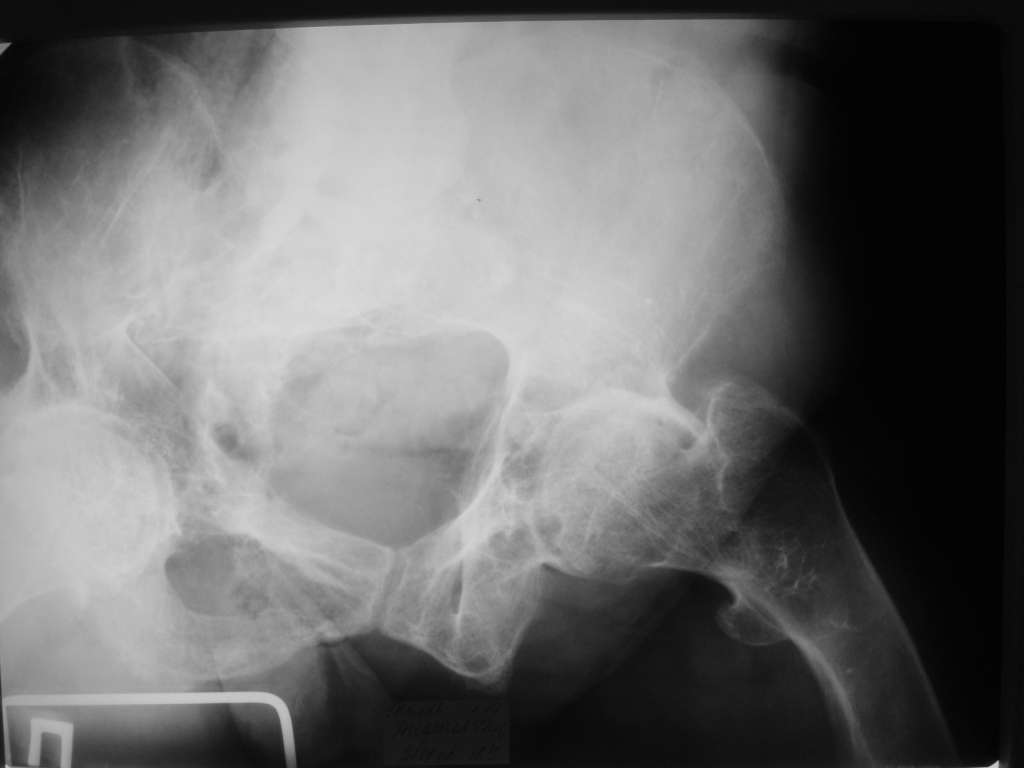

Уважаемые коллеги! Здравствуйте! Прошу у Вас совета вот по какому случаю.В нашу клинику поступила женщина 71 год. Травма в результате ДТП. (Пациентка передвигалась на инвалидной каляске и была сбита автомобилем). Диагноз: Множественная травма. Перелом нижней трети правого бедра. Перелом средней трети правой б/берцовой, малоберцовой кости, нижней трети левой большоберцовой, м/берцовой кости.Травматический шок. Со стороны внутренних органов и систем без патологии. Больная госпитализирована в реанимационное отделение, где было наложено двойное скелетное вытяжение за правую н/конечность. Левая н/конечность иммобилизована гипсовой лонгетой. Из анамнеза: больная является инвалидом 1 группы по опорно-двигательному аппарату. В детстве перенесла рахит. Осложнением которого "О" образная деформация нижних конечностей. Ограничено отведение нижних конечностей, деформирующий артроз тазобедренных и коленных суставов. В 1990 году перелом правого бедра остеосинтез пластиной. После операции больная передвигалась только на костылях или в инвалидной коляске.

Прошу прощения за качество снимков. Р-графия производилась в реанимационном отделении передвижным аппаратом.

Судя по Ro-граммах у больной скорее всего Vit-D

резистентный рахит и его последствия.Имеем наблюдения лечения остеопороза у данного контингента больных активными формами Vit-D -кальцитриол,даже в таком возрасте (положытельные результаты уже через 1-2 мес.).Фиксация фрагментов возможна внеочеговым аппаратом (самонарезные стержни в аппарате Илизарова).